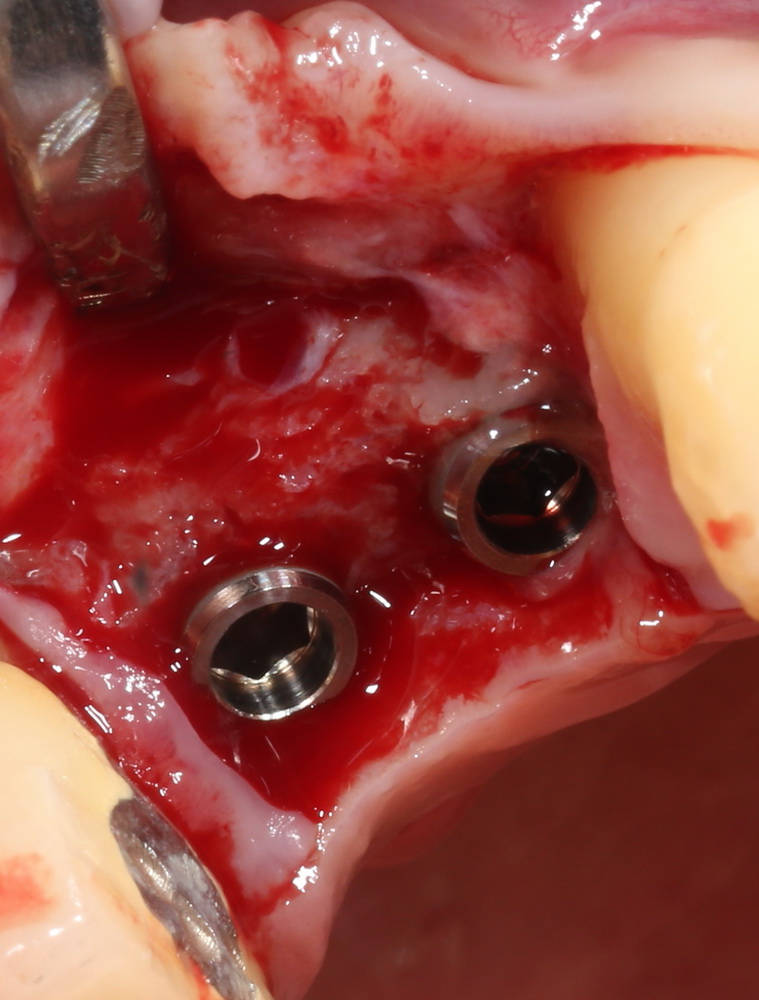

Синуслифтинг и имплантация

Конечная цель операции синуслифтинга – создание адекватных условий для установки имплантов. При этом, нередко удается провести имплантацию одновременно с операцией синуслифтинга. Как уже говорилось выше, это возможно, если существующий объем костной ткани позволяет стабилизировать имплантат заданного размера (рис 43, 44, 45):

Рисунок 43, 44, 45. Установка имплантов одномоментно с операцией синуслифтинга: слева – этап синуслифтинга, в центре – подготовка лунки под имплантат (виден спейсер и слизистая оболочка гайморовой пазухи), справа – установленный имплант